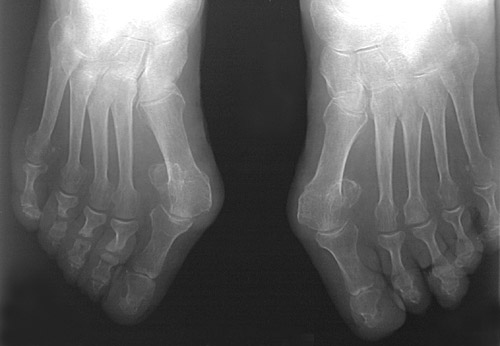

Both feet shown here reveal a deformity known as a bunion in which the first metatarsophalageal joint of the foot becomes very angled and prominent. This deformity produces difficulty in ambulating and in fitting shoes.